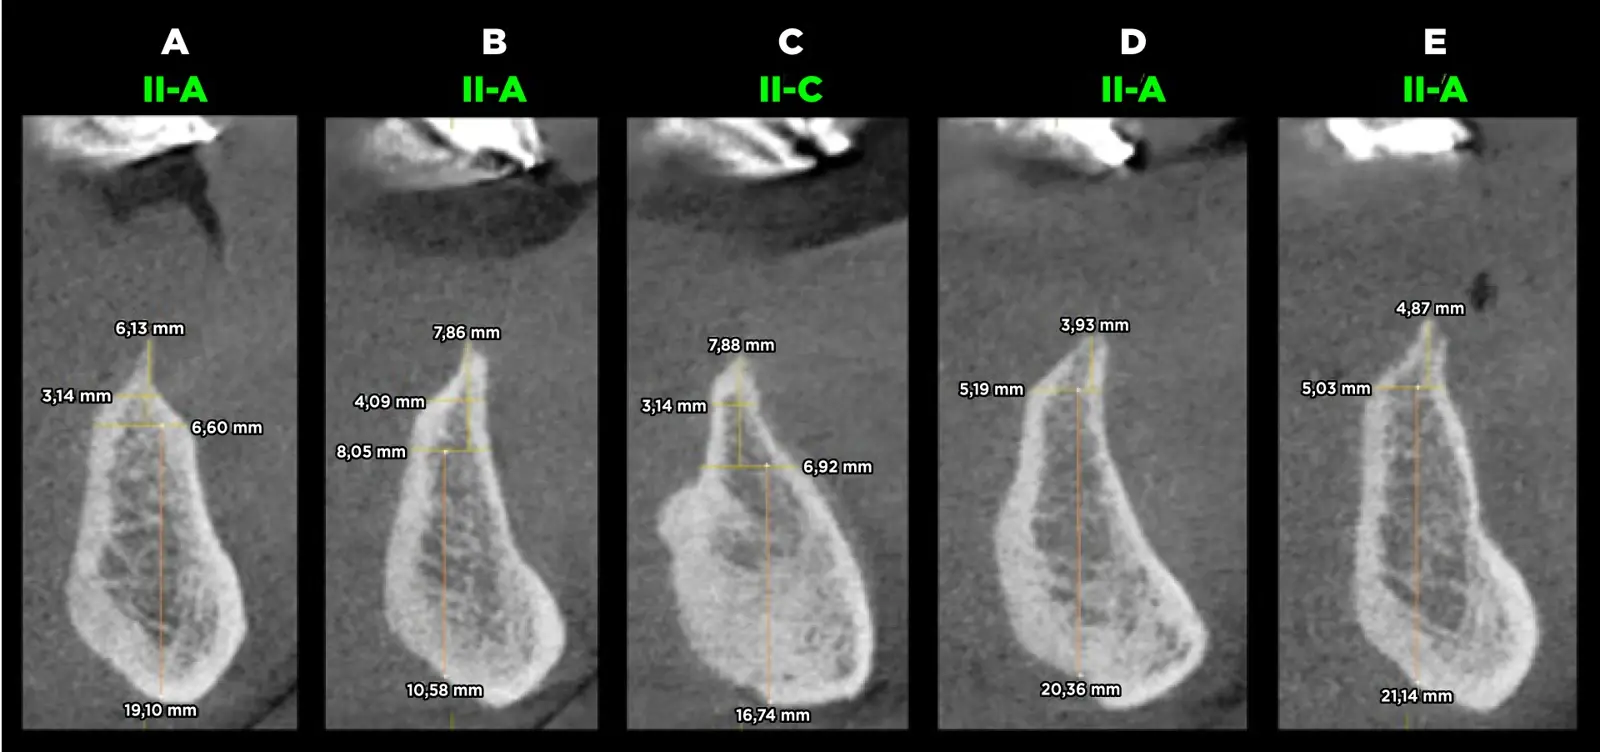

La calidad ósea es una de las variables más importantes que influye de manera directa en la estabilidad de los ID y es importante medir el grado de trabamiento de los implantes dentales en cada tipo de hueso. En 2022, Rosas y cols.5-7 presentan una modificación de la clasificación de calidad ósea de Lekholm y Zarb donde se considera la microestructura del patrón trabecular, el tamaño de los espacios medulares, los huesos regenerados y los huesos con patología:

Hueso Tipo II-A: hueso cortical grueso que rodea al hueso esponjoso de cantidad abundante con trabéculas nítidas en toda la imagen y presencia de espacios medulares pequeños y visibles5-10.

Hueso Tipo II-C: hueso cortical grueso que rodea al hueso esponjoso de cantidad abundante con predominio de trabéculas muy gruesas y nítidas en la basal, con presencia de espacios medulares pequeños y visibles. El tercio superior es parecido al II-B5-10.

Se procedió con la confección de la placa base y los rodetes de cera previa estabilización oclusal mediante un encerado de diagnóstico y planificación. Se confeccionó la guía quirúrgica bien adaptada y en oclusión para corroborar la ubicación tridimensional de los implantes. El paciente acudió a la consulta con una tomografía computarizada volumétrica previa a la confección de la prótesis inferior, en donde se realizaron los cortes tomográficos teniendo en cuenta los reparos anatómicos. Se evaluó la calidad ósea y se planificó la colocación de cinco implantes en posiciones A, B, C, D y E, con la eliminación previa de estructura ósea debido al escaso ancho que ésta presentó y que dificultaría la preparación e instalación de los implantes (Figura 3).